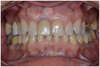

Femme de 45 ans venue consulter pour remplacer une incisive centrale perdue lors d’un choc. Sa dent est remplacée par un appareil amovible.

Un implant est positionné le matin et une empreinte est réalisée. Une couronne fixe est réalisée par le laboratoire pour le soir même

La dent provisoire est en place, elle est fixe, elle sera remplacée par une définitive quelques mois plus tard.